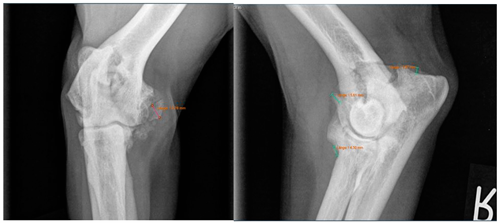

Moreover, Trochlear Notch Sclerosis (TNS), a radiological term denoting increased bone radio-opacity in the ulnar trochlear notch region, was quantified. The measurements adhered to the methodology outlined by Draffan et al. [

13], and the comprehensive TNS ratio of sclerosis to the ulnar depth was subsequently computed (

Figure 1). All measurements were performed by the first author of the article.

Viewing the TNS, both intra- and inter-individual calculations were carried out. Hence, for the intra-individual observations, the difference was calculated for each dog and the median was calculated from these results. Paired (intra-individual), the TNS had increased by 0.04 mm for the median of the arthroscopic-treated elbows. Without considering the intra-individual differences, the median TNS value for the arthroscopic-treated elbows was 0.47 mm pre-operatively and 0.53 mm post-operatively. The p-value showed statistical significance (p = 0.022) for the TNS value comparing the pre- vs. post-therapy conditions for this group. For the conservatively treated elbows, the median TNS did not change when the intra-individual differences were formed (comparing before and after therapy; median = 0), but without considering the intra-individual differences, the median TNS value pre-operatively was 0.45 mm and post-operatively 0.50 mm. There was no significant difference in the TNS value of the elbows treated conservatively (p = 0.228). If the TNS value increased intra-individually, the enlargement was quite more evident compared to the elbows, with a reduction in the TNS value (maximum reduction in the TNS value is stratified after conservative or arthroscopic treatment at 0.07 mm or 0.08 mm, respectively, whereas the maximum enlargement is 0.12 mm or 0.20 mm, respectively).